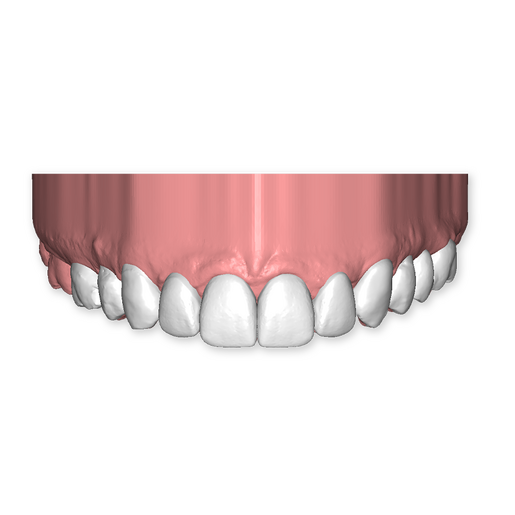

The DSD Interdisciplinary is a digital wax up of the upper and lower arches, designed considering a facially-driven, clinical and functional analysis of the patient.

It includes the diagnostic findings, treatment plan suggestions, a 2D smile design simulation, and most importantly, a Live Treatment Planning (LTP) session with one of our clinical experts to go through the case, brainstorm our suggestions, discuss treatment sequencing, and make any necessary and/or requested modifications.

Our 3D simulations showcase various treatment suggestions, facilitating a deeper understanding of the required procedures. This leads to the creation of a broader treatment plan and enables a more efficient communication with your patients.